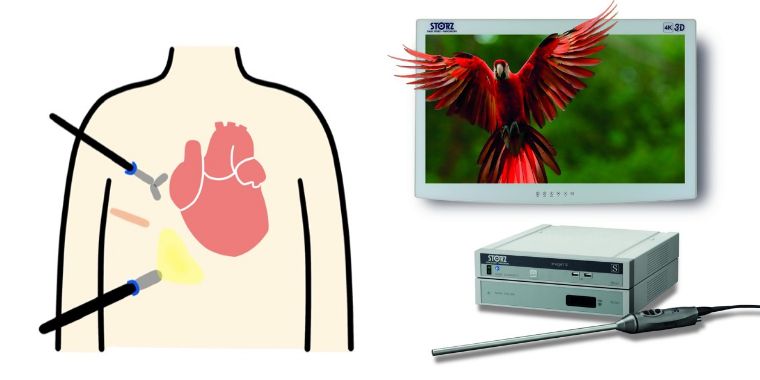

当院でのMICS手術では、主に3D内視鏡というカメラと特殊メガネを使用しています。

拡大され立体視となった画面を見ながら、肉眼では確認できない部位まで詳細に把握し手術を行っております。